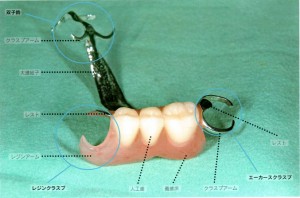

つまり、一般のパーシャルデンチャーで歯に掛ける金属部分(クラスプ)が、義歯床用の樹脂でできている(レジンクラスプ)パーシャルデンチャーのことをいいます。ノンメタルクラスプデンチャーには全く金属を使っていないものだけでなく、部分的に金属が使われているものも含まれます。